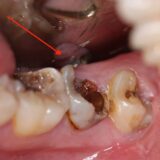

- Sâu kẽ răng hàm: Khi kẽ răng hàm bị sâu, do vị trí răng hàm nằm sâu bên trong nên rất khó để nhận biết ở giai đoạn đầu. Nhiều người chỉ phát hiện khi bệnh đã tiến triển nặng, lan rộng và ảnh hưởng đến các răng bên cạnh.

- Sâu ngà sâu: Đây là giai đoạn nặng nhất khi bị sâu răng. Lớp men răng và ngà răng đã bị vi khuẩn ăn mòn nghiêm trọng, có thể ảnh hưởng đến tủy răng và vùng nướu. Các cơn đau nhức thường xuất hiện thường xuyên hơn và kéo dài hơn ở giai đoạn này.